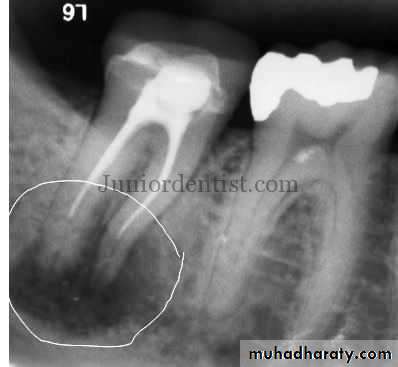

Radiographic changes may occur, ranging from a thickening of the periodontal ligament space to the appear-

ance of a periapical radiolucent lesion

Teeth with acute apical periodontitis are usually symptomatic and painful to bite and percussion which results from mechanical allodynia and hyperalgesia.Radiographic examination usually does not show periapical bone destruction of the involved tooth in acute apical periodontitis, although occasional slight widening of the apical periodontal ligament space and loss of the apical lamina dura of the involved tooth may be present.

Abscess is a focal localized collection of purulent exudate in a tissue or an organ

Acute Apical Abscess

Acute apical abscess (AAA) is a localized or diffuse liquefaction lesion of pulpal origin that destroys periradicular tissues and a severe inflammatory response to microbial and nonbacterial irritants from a necrotic pulp.The development of an abscess in apical periodontitis lesions is probably caused by invasion of a combination of specific pyogenic bacteria in the inflamed periapical tissues.